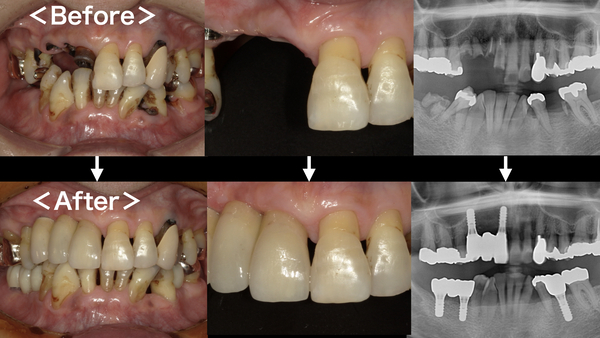

こちらが初診時のお口の中の写真となります。

右上の前歯の差し歯が取れてしまい、根っこだけが残ってしまっている状態です。

右下・左下にも同じように根っこだけの歯がいくつかあります。

こちらがインプラント終了後のレントゲン写真になります。

無事に計画通り5本のインプラントが入りました。

こちらがセット後の写真になります。